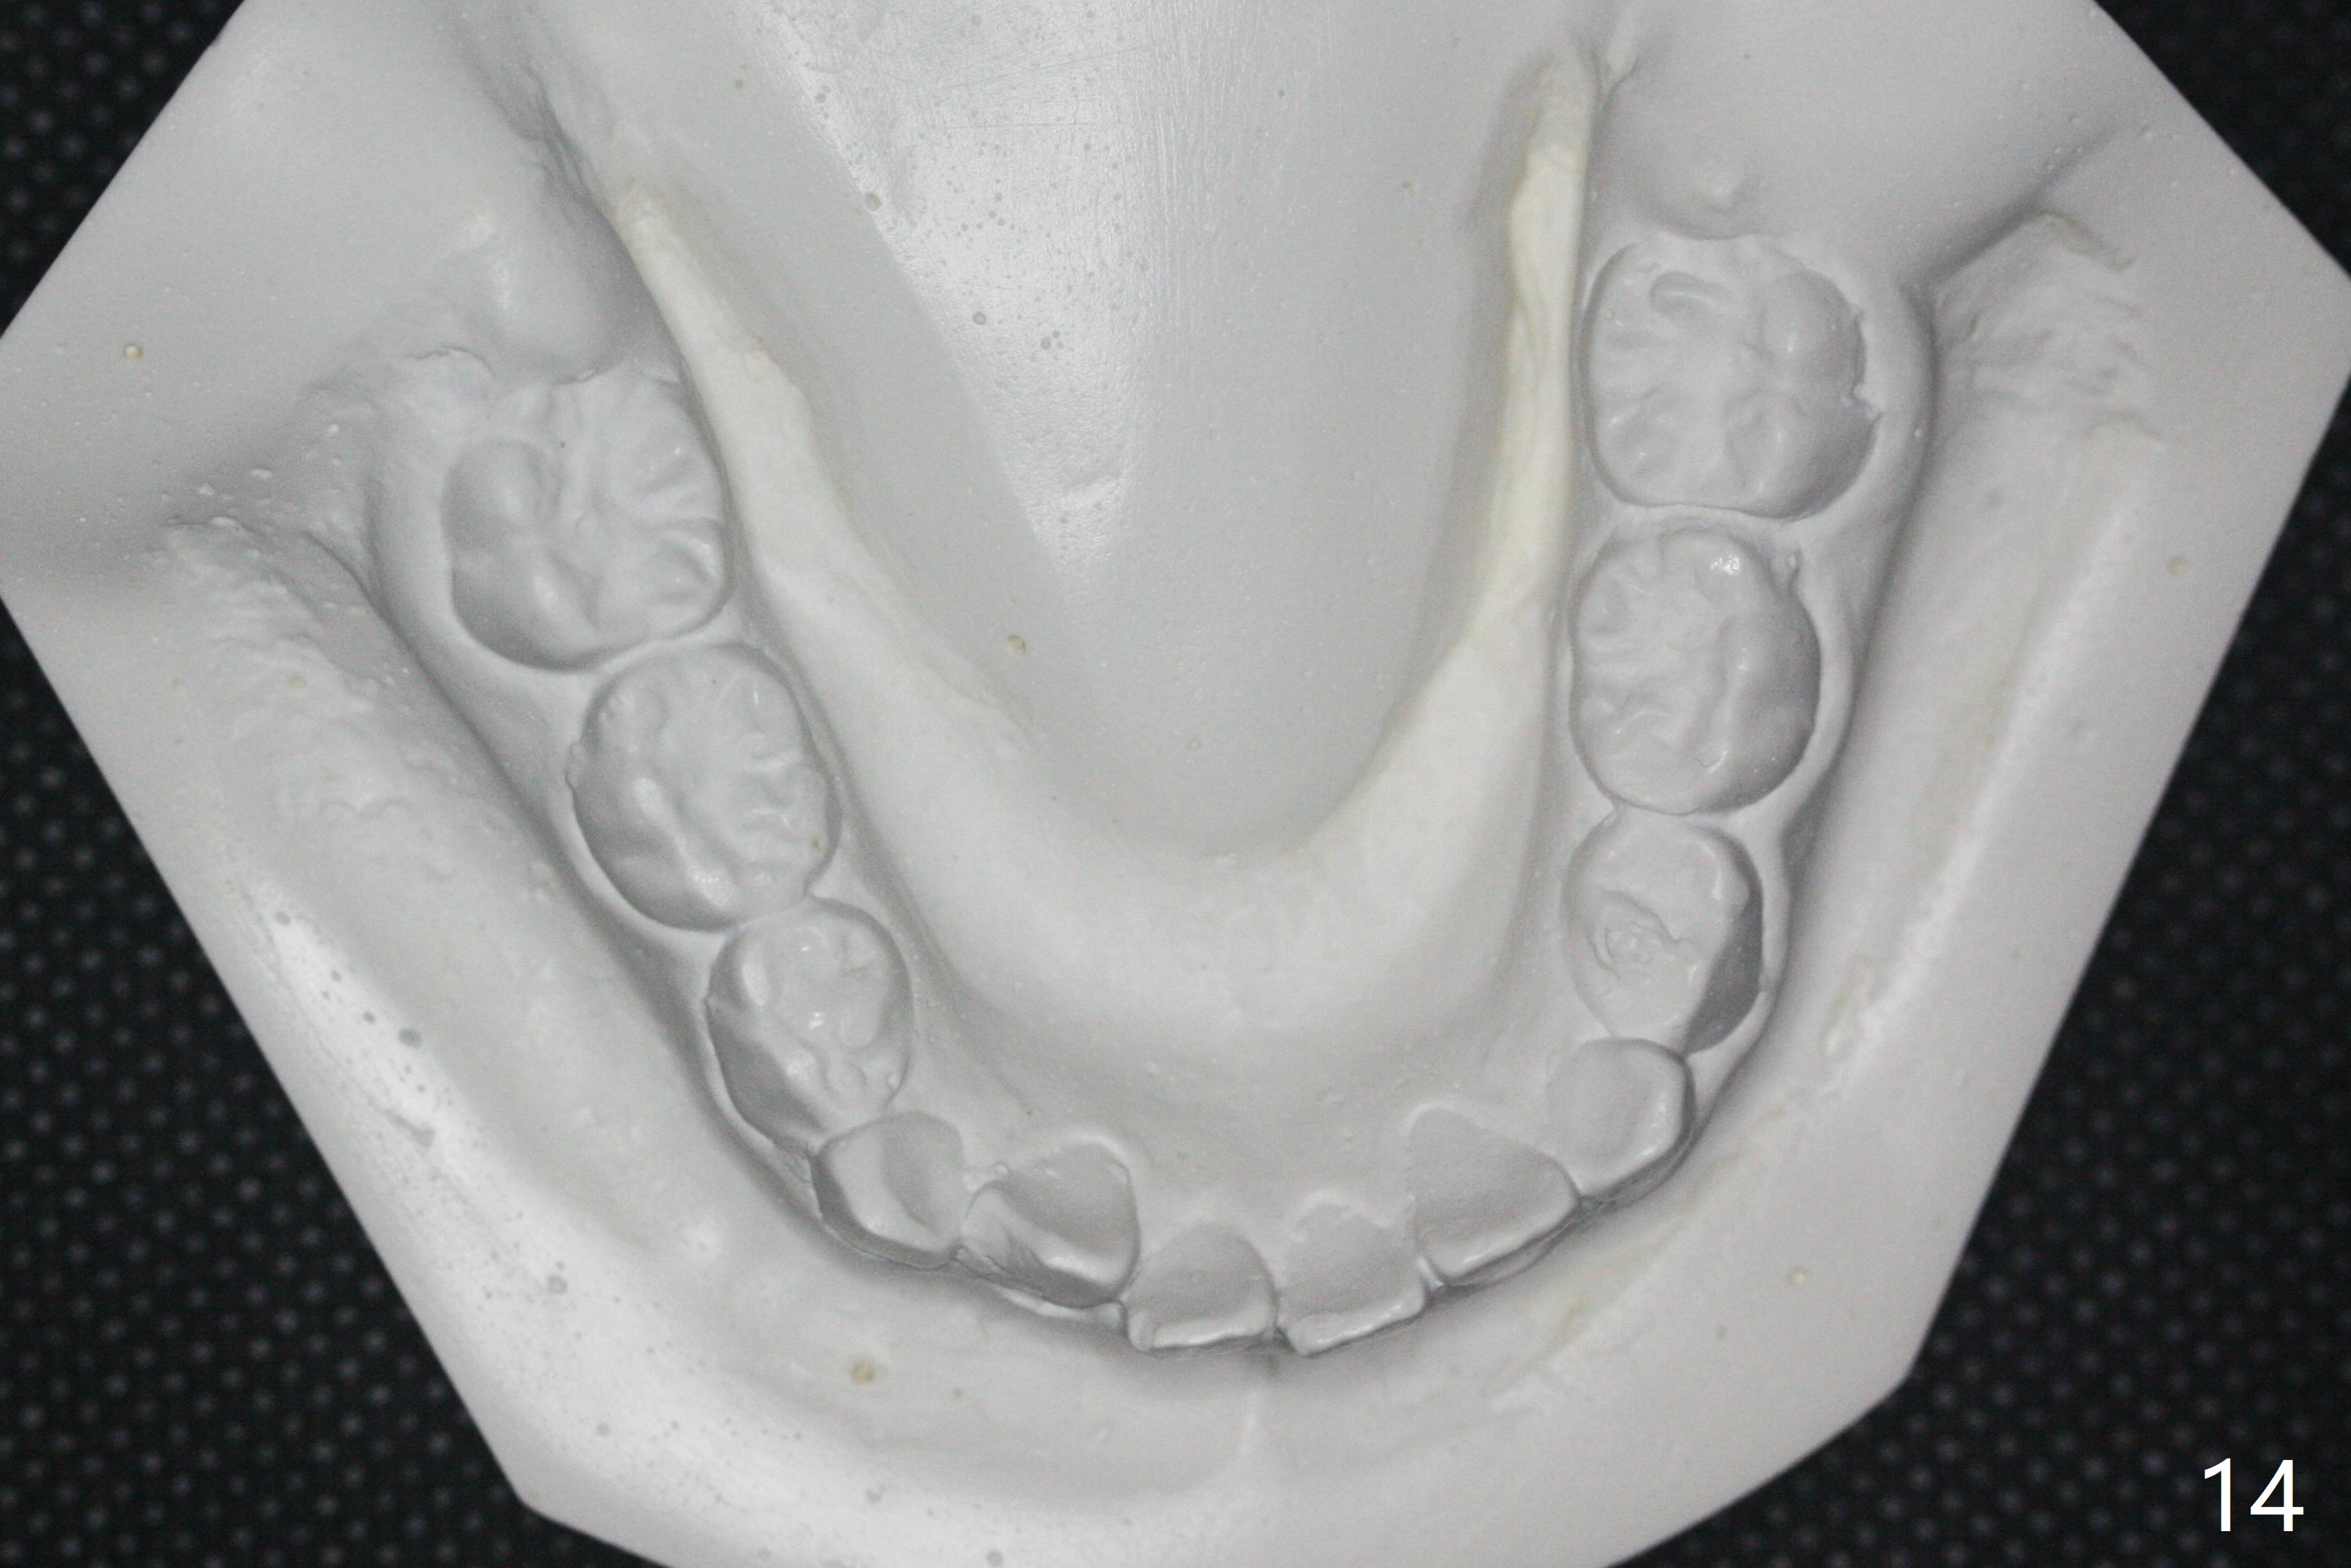

7岁女孩龋齿(图一)到八岁发展的严重(图二,三 (D))。为了有完整支抗,利用树脂(而不是不锈钢牙冠)保留左上第一乳磨牙(图六:D),以后可以安置矫正器。面部匀称(图七至十)。乳尖牙,第一恒磨牙:第一类咬合(图十一,十二)。左上前牙拥挤比右边轻,因为左上D龋齿破坏(图十三:D)。前牙扩弓时,右上D近中需要片切(^)。下颌拥挤轻(图十四),矫正器可以迟放置。